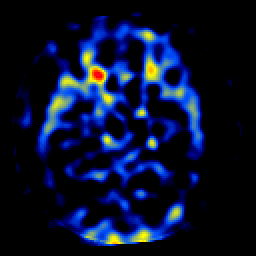

SPECT TL Study #7 -- Slice #24

[Home][Help][Clinical][Tour 1][Tour 2][Tour 3] Slice 24